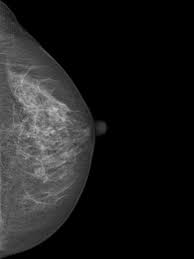

Mammography Wikipedia from upload.wikimedia.org Even if you have a lump in only one breast, pictures will be taken of both breasts. However, in rare cases, breast cancer can be the cause of gynecomastia so, a full mammographic investigation is always necessary. Dense breast tissue appears solid. 1 the gray areas correspond to normal fatty tissue, while the white areas are normal breast tissue with ducts and lobes. This overlapping tissue can cause the resulting image to look like cancer. After a mammogram that didn't show anything, and a sonogram that found the lump, i was diagnosed with stage 2 breast cancer. This is why you should always talk to your doctor if you notice an unexplained change in the size of a breast. We'll show you breast cancer pictures to help you identify any physical traits of the condition.

Essentially, mammograms turn a 3d object into a 2d object. This is why you should always talk to your doctor if you notice an unexplained change in the size of a breast. What does the doctor look for on a mammogram? cancer.org. A screening mammogram is performed at regular intervals to check for breast cancer in women who have no signs or symptoms of the disease. Bright spots on a mammogram that look like potential tumors could turn out to be overlapping tissues or a blood vessel folding over on itself, friedewald said. To license this video for patient education or content marketing, visit: What does breast cancer look like? This overlapping tissue can cause the resulting image to look like cancer. Finding breast lumps and seeing change in the size and shape. Screening mammograms have been used since the 1980s. Digital breast tomosynthesis (tomo), also known as 3d mammography, is a revolutionary new screening and diagnostic breast imaging tool to improve the early detection of breast cancer. Ultrasound characterization of breast masses. indian journal of radiology and imaging. Calcifications are calcium deposits within the breast tissue and they look like small white spots.

Moose & doc breast cancer, 21 may 2018. We'll show you breast cancer pictures to help you identify any physical traits of the condition. Normal breast tissue can look 100,000 different ways on a mammogram. Finding breast lumps and seeing change in the size and shape. Dense breast tissue appears solid. Essentially, mammograms turn a 3d object into a 2d object. American cancer society, 9 oct 2017. That makes it easy to detect abnormalities, which generally show up as white. A 3d mammogram is used to look for breast cancer in people who have no signs or symptoms. More importantly, the overlap can obscure small breast cancers. A screening mammogram is performed at regular intervals to check for breast cancer in women who have no signs or symptoms of the disease. Several patterns of calcifications are seen with dcis, including: Breast cancer and some noncancerous (benign) breast conditions can appear white on a mammogram.

More Breast Cancers Detected With 3d Mammography National Breast Cancer Foundation Nbcf Donate Online from 1o2l7w1aqqrk1f987e40vzis-wpengine.netdna-ssl.com This overlapping tissue can cause the resulting image to look like cancer. Several patterns of calcifications are seen with dcis, including: The look of breast cancer on a mammogram a tumor or lump will appear as a focused white area on the mammogram. Most screening mammograms include two views of each breast taken from different angles. Specialist doctors (radiologists) trained to interpret mammograms can identify any abnormal areas, masses or calcium. What does breast cancer look like on a mammogram? A tumor that is benign, it is not a health problem and it may not grow or change shape. Ultrasound characterization of breast masses. indian journal of radiology and imaging.

Breast cancer and some noncancerous (benign) breast conditions can appear white on a mammogram. This overlapping tissue can cause the resulting image to look like cancer. Diagnostic mammograms involve taking more views than screening mammograms. It's so important to listen to the messages our bodies are telling. A number of studies have found that 3d mammograms find more cancers than traditional 2d mammograms and also reduce the number of false positives. Ultrasound characterization of breast masses. indian journal of radiology and imaging. Even if you have a lump in only one breast, pictures will be taken of both breasts. Finding breast lumps and seeing change in the size and shape. 1 the gray areas correspond to normal fatty tissue, while the white areas are normal breast tissue with ducts and lobes. A false positive is when a mammogram shows an abnormal area that looks like a cancer but turns out to be normal. Breast cancer can appear as a spiculated mass, cluster of tiny calcifications, smoothly marginated mass, area of subtle distortion or be invisible on. Macrocalcifications, which look like small white dots on a mammogram. One advantage of ultrasound technology is that it allows substantial freedom in obtaining breast images from any orientation.